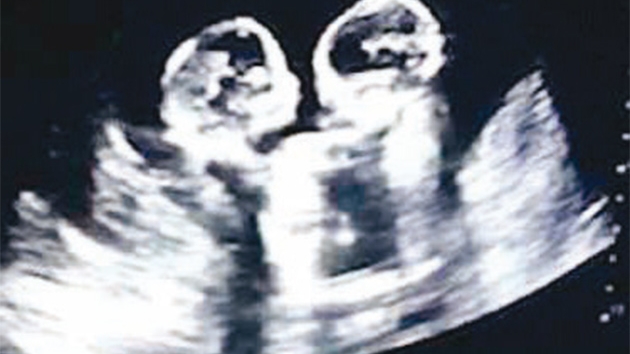

Çin'in Yinchuan şehrinde anne karnında aynı kesede bulunan ikiz bebeklerin daha doğmadan kavgaya tutuştuğu ultrason görüntüleri internette viral olmuştu.